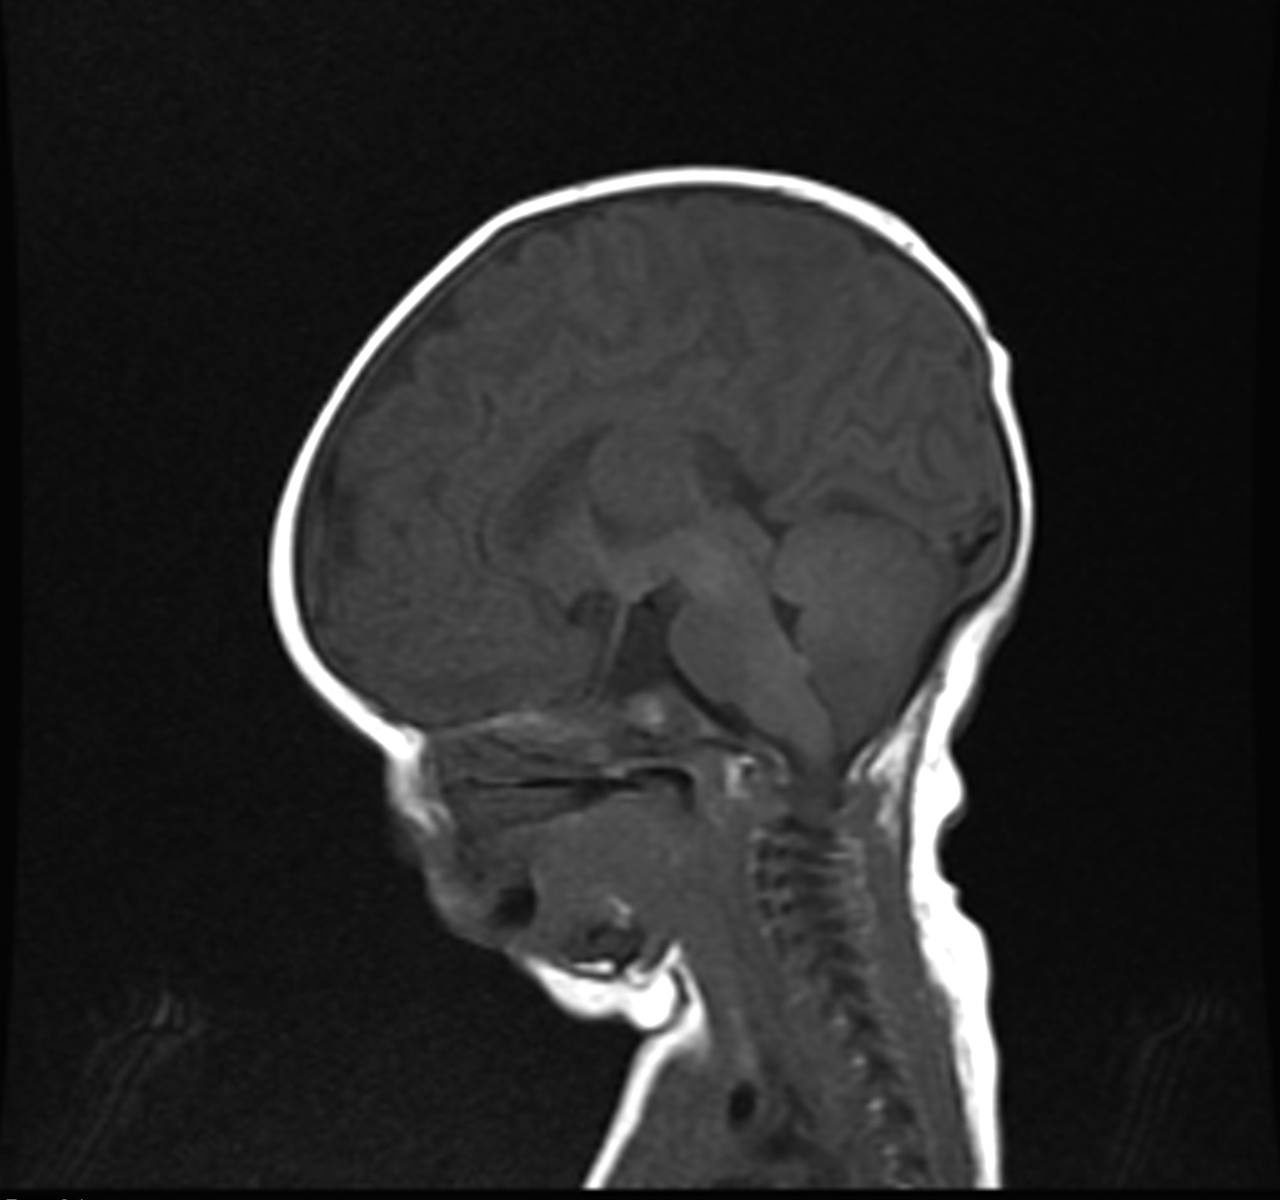

MRI findings showed the lack of the normal flow void of the left internal carotid canal and the first part of the left middle cerebral artery (Figures 1 and 2). The pituitary gland is flat. No evident anterior or posterior pituitary gland tissue or pituitary stalk is observed. The pituitary gland's strong posterior signal is not detected in situ or

ectopic. The left medial cerebral artery originates within the posterior circulation, and the left internal carotid artery cannot be seen. No intra, supra, retro or parasellar masses. Normal MRI appearance of the optic chiasm and corpus callosum. Otherwise, normal MR appearance of the brain parenchyma with no definite focal lesions. Diagnosis of congenital panhypopituitarism associated with agenesis of ICA was made.

a)

b)

c)

d)

Figure 1. a-c) figures showing MRI brain sagittal views of the patient where the pituitary sella is flat. No obvious anterior or posterior pituitary gland tissue or pituitary stalk is seen. The posterior pituitary bright signal is not visualized in site or ectopic. d) coronal MRI scan showing absence of pituitary gland tissue.

Generally, no intra, supra, retro, or parasellar masses. Normal MRI appearance of the optic chiasm and corpus callosum. Otherwise, normal MR appearance of the brain parenchyma with no definite focal lesions.